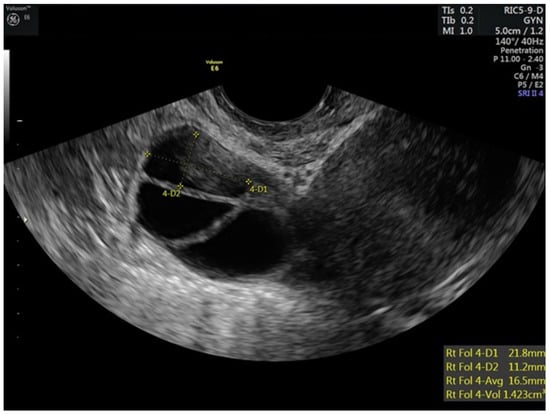

| 7 | 5 | 40 | 100 | 75 | 250 | 84 | 12,11,10,9,9,7 | 12,12,11,10,9,8 | 4.7 | |||

| 8–9 | 5 | 40 | 100 | 75 | 250 | 116 | 15,14,13,11,10,9 | 16,14,13,13,12,7 | 5.8 | |||

| 10 | 5 | 40 | 100 | 75 | 250 | 172 | 0.6 | 19,17,17,13,12,12,9,6 | 18,17,16,16,13,4 | 5.3 | ||